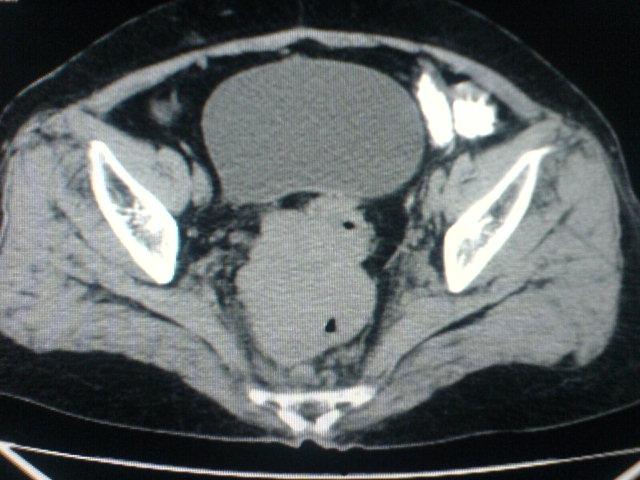

患者为老年女性,肿块最大层面不是位于宫颈,但宫颈偏后方有一囊状低密度影,肿块主要位于乙状结肠及直肠,所以考虑乙状结肠及直肠癌浸犯宫颈可能性大。

患者女性60岁 病史不详

宫颈癌侵犯直肠可能

考虑子宫内膜癌浸犯直肠。

考虑直肠癌侵及宫颈可能;建议增强扫描。

支持考虑宫颈癌上下前后通吃

考虑:直肠及乙状结肠癌侵及宫颈,囊性转移(假性粘液瘤)

支持宫颈癌侵犯直肠。

考虑直肠及乙状结肠癌侵犯邻近结构。